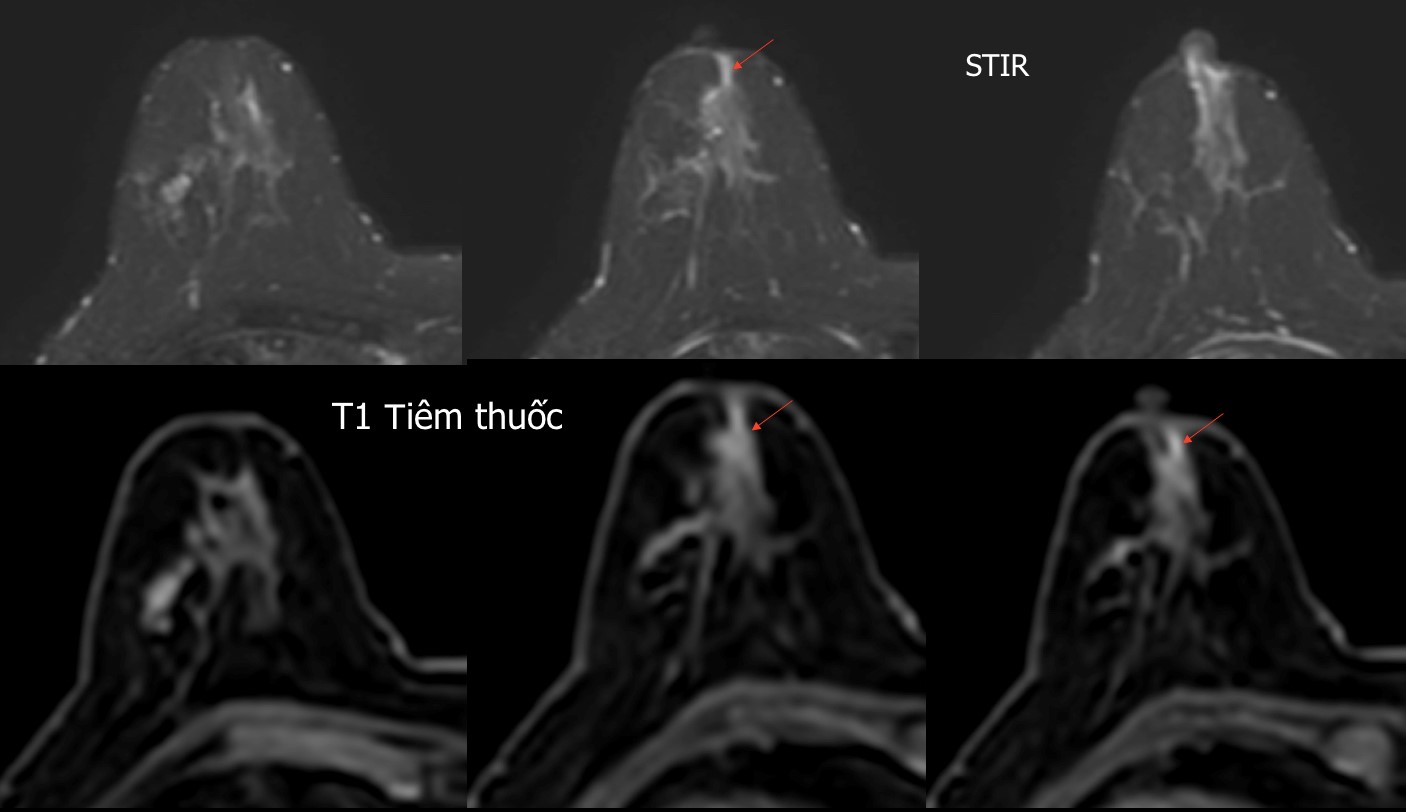

Hình ảnh CHT tuyến vú

BN 62 tuổi, đi khám vì chảy dịch núm vú, siêu âm và Xq tuyến vú bình thường, trên ảnh CHT thấy có ống tuyến ngấm thuốc (hình mũi tên đỏ), chẩn đoán trên ảnh CHT có tổn thương ở ngay dưới núm vú phải, kết quả sau mổ: ung thư biểu mô ống xâm nhập.